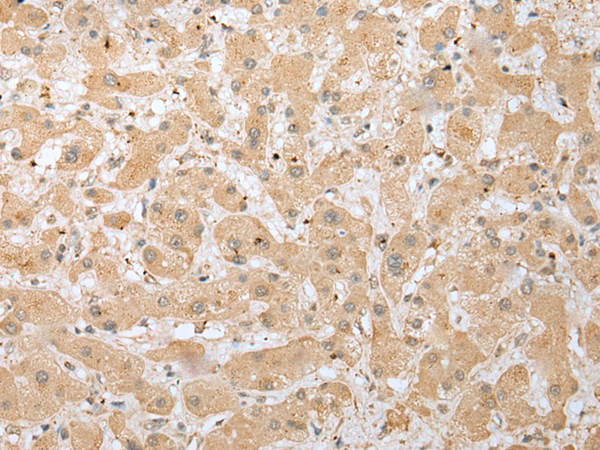

IHC positive control: |

Human liver cancer and Human lung cancer |

IHC Recommend dilution: |

25-100 |